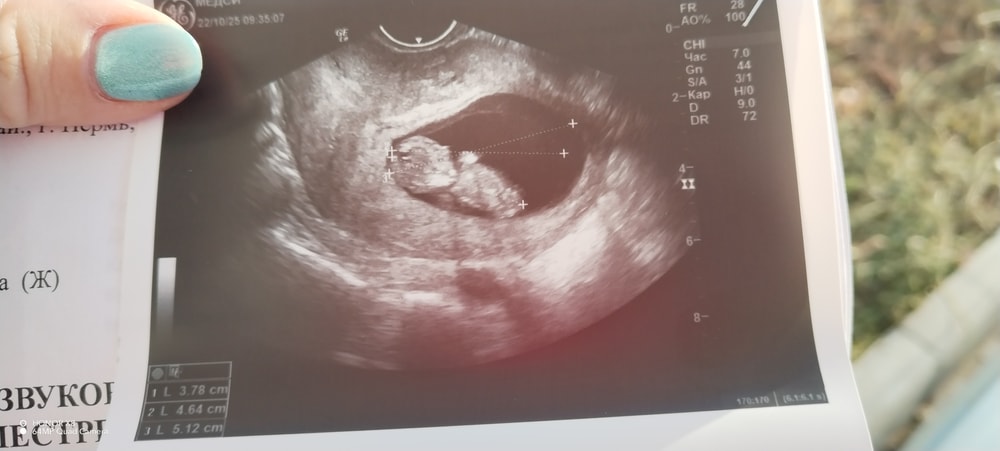

10 недель 2 дня

Наши будни, наши неделькиТоксикоз отпустил, но после того, как покушаю неприятные ощущения в животе. Хочется, как будто бы сходить и 🤮. Начала немного возвращать сладкое в свой рацион, но это в основном только зефир от остольного воротит. Ходила сегодня на узи. Моя булка выросла ктр 37.8мм, органы все сформированы сказала: перестать уже бегать на узи и дождаться скрининга. По узи всё отлично ❤️ я вышла на работу после больничного. Очень не хочется работать, я постоянно хочу спать, полежать, понежиться под одеялом. Вкусовые предпочтения не поменялись. Нет конкретного продукта, которого я бы ела и ела. Ночью стала 2-3 раза просыпаться, чтоб сходить в туалет. Грудь то болит, то не болит. Появились стреояющие боли в матке и у пупка тянет, читала, что так растёт матка. В целом всё хорошо ❤️